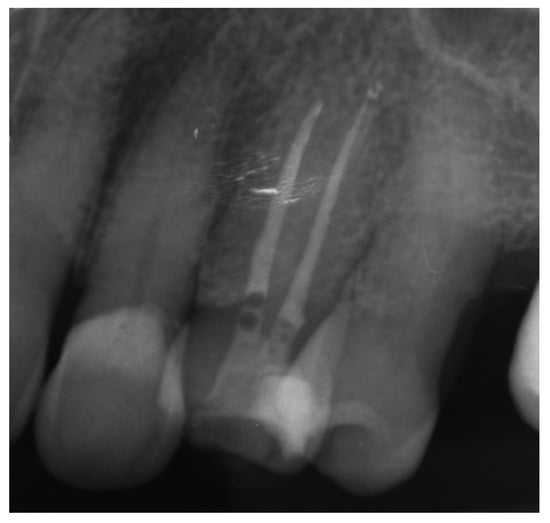

A 39-year-old male patient was referred to an endodontic specialist for the treatment of a maxillary left central incisor (tooth 21) before prosthetic treatment. Endodontic treatment had been initiated by the referring dentist, but as it was impossible for the clinicians to localize the root canal under the optical microscope, the treatment could not be completed, and the patient was referred to a specialist. The patient’s medical history revealed the absence of any systemic disorders or allergies. The dental history revealed trauma to the maxillary anterior region in childhood and subsequent gradual discolouration of the maxillary left central incisor. The patient presented with no complaints. Clinically, there were no pain or sensitivity to percussion or palpation. Tooth mobility was not increased. The tooth was restored by the referring dentist with a temporary restoration (composite resin) and showed no response to the pulp sensibility test (cold test). The radiograph and CBCT images showed that the endodontic treatment was initiated with wide access in the coronal part and confirmed root canal obliteration (Figure 16). After discussing the high probability of perforation and further tooth substance loss, an endodontic guide was designed.

Figure 16. The failed wide access in the coronal part and root canal obliteration on (a) X-ray and (b) CBCT images.